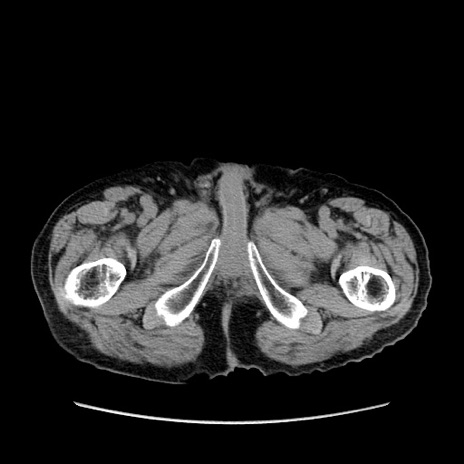

症例24(横断像)

【症例】80歳代男性

【主訴】左側腹部痛、嘔吐

【現病歴】本日早朝より左腹部に痛みあり。昼頃嘔吐認めたため、救急要請。

【既往歴】直腸癌(Mile手術)、胆摘

【身体所見】意識清明、BT 35.9℃、BP 221/93mmHg、SpO2 97%(RA) 、腹部:左ストーマ周囲に限局性の腹部膨隆あり。 膨隆部自発痛・圧痛あり・軟。

【データ】WBC 7700、CRP 0.09